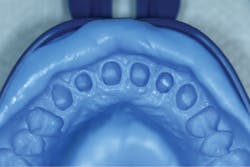

Upon achieving local anesthesia, an impression was made for provisional crown fabrication using a triple tray and monophase VPS impression material (V-Posil Mono Fast , Voco; figure 9). The tooth was then prepared for a crown using a flowable, dual-curing, nano-hybrid core build-up material (Grandio Core Dual Cure, Voco; figure 10).

Figure 9: Impression for provisional crown fabrication

A final impression was made using a base VPS impression material (V-Posil Putty Fast, Voco; figure 11) followed by a light-body VPS impression material wash (V-Posil Light Fast, Voco; figure 12). A provisional crown was made using a cold-cure composite provisional material (Structur 3, Voco; figures 13 and 14) andcemented. The patient was dismissed. Upon return three weeks later, the provisional was removed and the definitive laboratory-fabricated zirconia crown was delivered.

Figure 13: Making of provisional crown